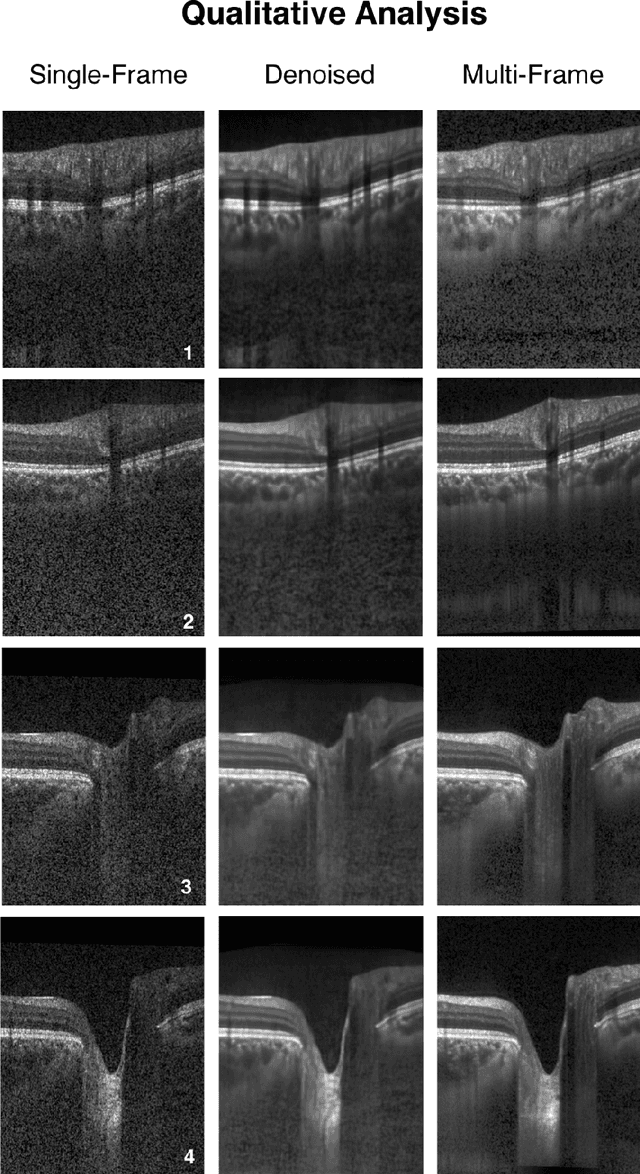

Abstract:Purpose: To develop a deep learning approach to de-noise optical coherence tomography (OCT) B-scans of the optic nerve head (ONH). Methods: Volume scans consisting of 97 horizontal B-scans were acquired through the center of the ONH using a commercial OCT device (Spectralis) for both eyes of 20 subjects. For each eye, single-frame (without signal averaging), and multi-frame (75x signal averaging) volume scans were obtained. A custom deep learning network was then designed and trained with 2,328 "clean B-scans" (multi-frame B-scans), and their corresponding "noisy B-scans" (clean B-scans + gaussian noise) to de-noise the single-frame B-scans. The performance of the de-noising algorithm was assessed qualitatively, and quantitatively on 1,552 B-scans using the signal to noise ratio (SNR), contrast to noise ratio (CNR), and mean structural similarity index metrics (MSSIM). Results: The proposed algorithm successfully denoised unseen single-frame OCT B-scans. The denoised B-scans were qualitatively similar to their corresponding multi-frame B-scans, with enhanced visibility of the ONH tissues. The mean SNR increased from $4.02 \pm 0.68$ dB (single-frame) to $8.14 \pm 1.03$ dB (denoised). For all the ONH tissues, the mean CNR increased from $3.50 \pm 0.56$ (single-frame) to $7.63 \pm 1.81$ (denoised). The MSSIM increased from $0.13 \pm 0.02$ (single frame) to $0.65 \pm 0.03$ (denoised) when compared with the corresponding multi-frame B-scans. Conclusions: Our deep learning algorithm can denoise a single-frame OCT B-scan of the ONH in under 20 ms, thus offering a framework to obtain superior quality OCT B-scans with reduced scanning times and minimal patient discomfort.